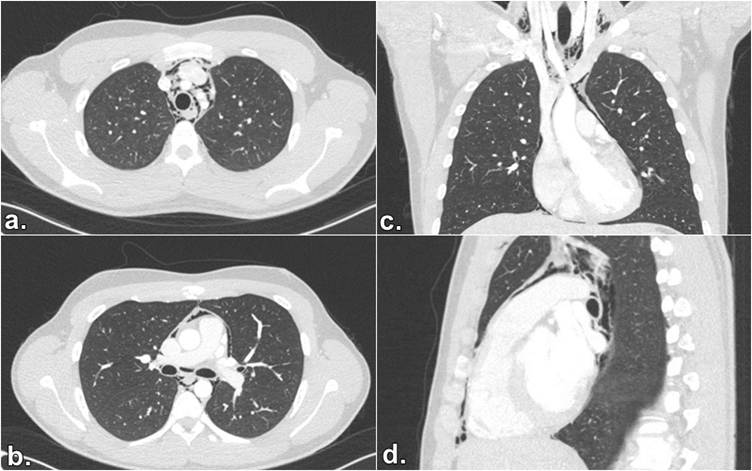

Se trata de un adulto joven de 20 años, sin antecedentes clínicos de importancia. Ingresa al servicio de urgencias consultando por cuadro clínico de 3 días de evolución consistente en dolor de cuello que se irradia al tórax con sensación pleurítica, refiere que el cuadro clínico ignición posterior a la ingesta de una tableta de azitromicina con un líquido espeso. Además, refiere que con el uso del vapeador aumentó inicialmente la sintomatología y después le fue aliviando. Al examen físico ingresa con signos vitales dentro de parámetros normales se palpa enfisema subcutáneo en región supraclavicular derecha y en cuello anterior derecho, por lo que se realiza radiografía de tórax, la cual se reporta dentro de parámetros normales. Paraclínicos de extensión con hemograma el cual revela leve leucocitosis y neutrofilia, sin anemia, función renal conservada. Se indica la toma de tomografía de cuello y tórax contrastada con el fin de descartar lesión de la vía aérea. (Fig.1y2) La tomografía describe enfisema subcutáneo que compromete base del cráneo, cuello derecho, región supraclavicular, paravertebral y axilar derecha que diseca planos musculares sin evidenciarse claramente origen de la lesión. Por otra parte, la tomografía contrastada de tórax muestra un neumomediastino extenso, probablemente espontáneo, sin garantizar que no hay una perforación esofágica asociada. Se valora paciente en conjunto con servicio de Emergenciología, Neumología y Cirugía de tórax, por lo que se indica traslado a la Unidad de Cuidado Intensivo (UCI), con la finalidad de vigilar vía aérea del paciente y realizar exámenes afines que complementen el cuadro clínico del paciente; se indica entonces realización de esofagograma (Fig. 3), endoscopía de vías digestivas altas y fibrobroncoscopía.

Fig. 2: Tomografía de tórax contrastada del paciente. a,b: Se observa neumomediastino que diseca estructuras de mediastino anterior medio y posterior. c:Se observa en corte coronal neumomediastino desde la región cervical que diseca parades cardíacas. d: neumomediastino extenso sin garantizar perforación esofágica.